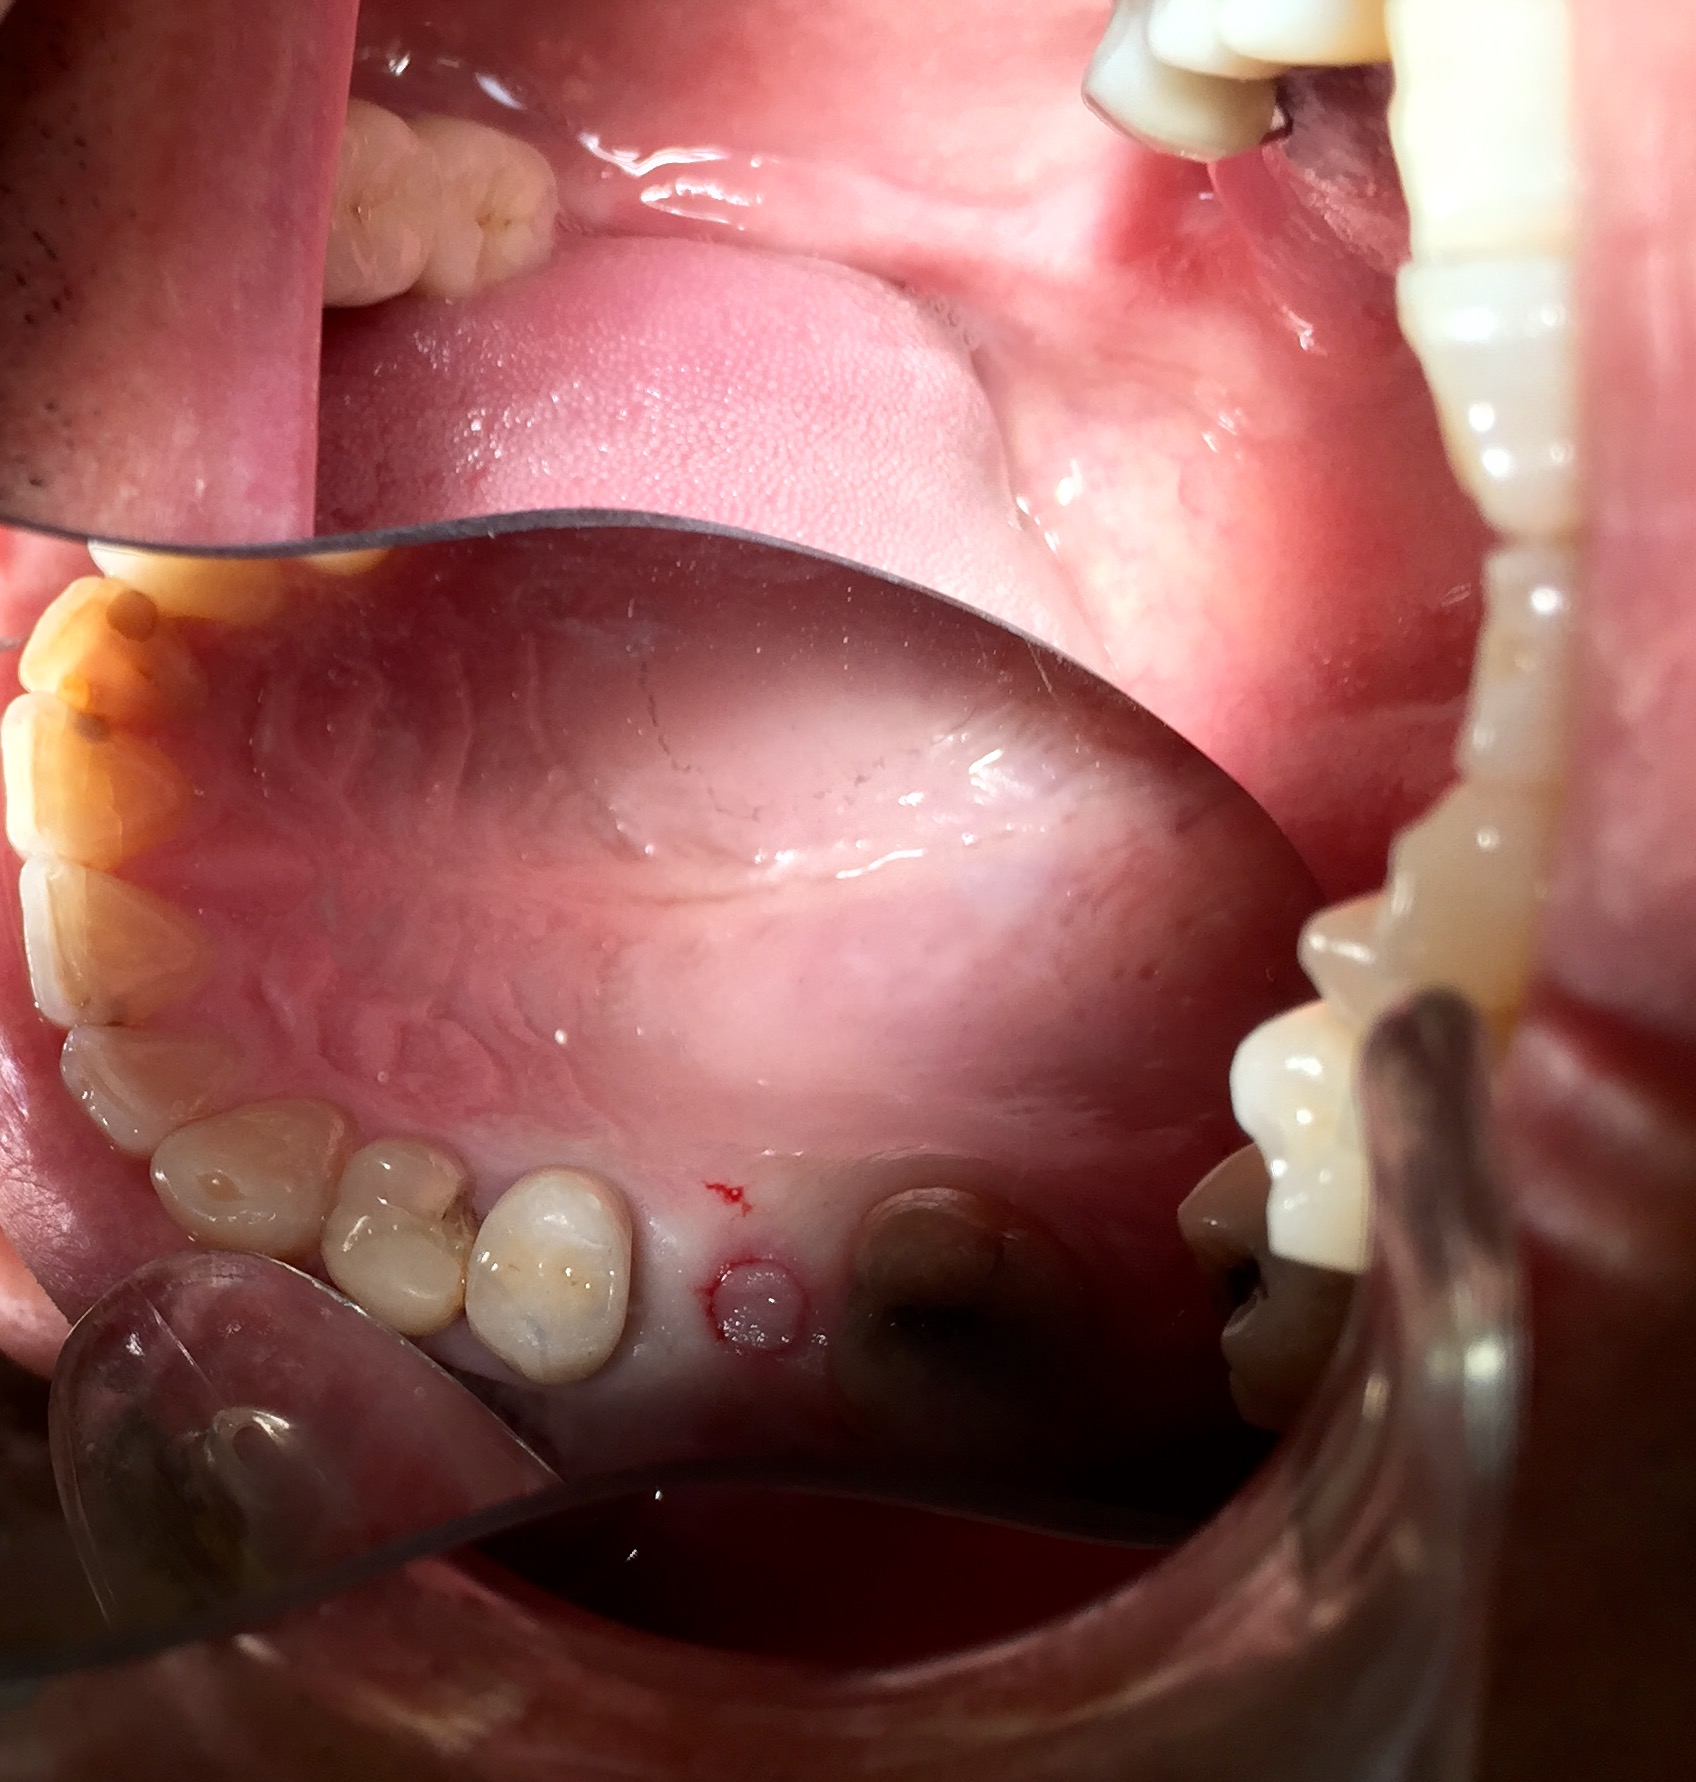

Protesi mobile dell' Arcata inferiore